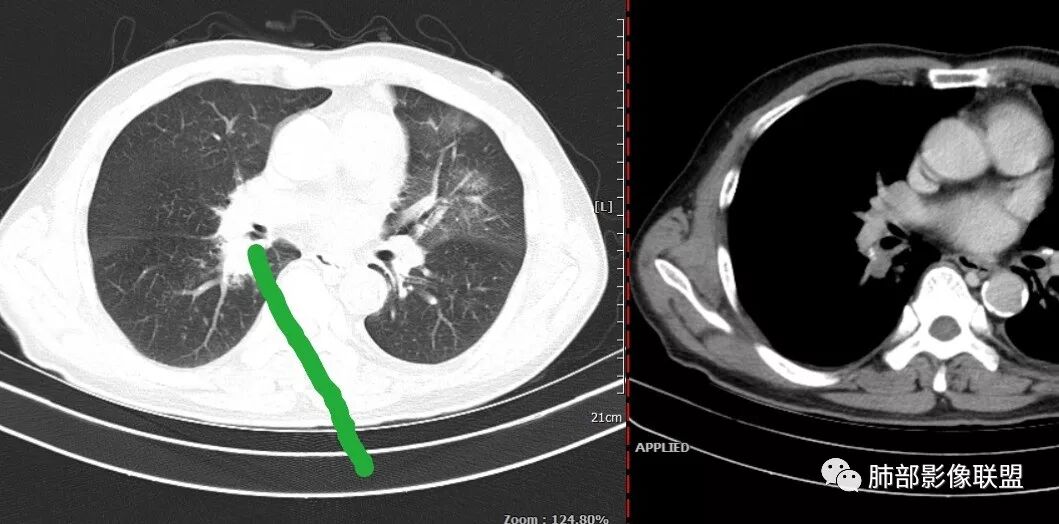

老年男性,有糖尿病4年,长期咳嗽;这次咳嗽5天,左胸痛2天

这个病灶如何考虑?

纵膈淋巴结以钙化为主。

这个壁厚,但是支气管软骨连续。

背段支气管有问题,局部有结节

膈面上还有一个结节

总共4处病灶,如何考虑?

左上叶肿瘤?炎性?

还有少量胸水。

南边:

第一个问题:左上叶考虑炎症?癌?

实变区:

实变区边缘收缩,部分区域紧贴纵隔胸膜。

胸膜下有间隙

南边老师思路分析

左肺上叶病灶长轴与支气管走形一致,提示沿支气管分布病变,倾向于炎性,大家可能怀疑这个病例是来源于胸膜下为主的,胸膜下来源首先整体是来源于胸膜下,与胸膜下之间没有间隙,而这例与胸膜下有间隙。而且这个病变是沿支气管朝外蔓延的,而胸膜下来源的是朝内蔓延的,唯一给我们错觉的是靠近纵隔胸膜这个地方有问题。但是靠近纵隔胸膜这个位置实变不是靠近胸膜实变,它边缘收缩的,没有膨隆的迹象。我们看到里面支气管直达远端稍扩张,是以中央间质为主、小叶间隔朝外蔓延,有间质也有实质病变,走向是沿中央间质方向走的,我个人倾向炎性病变。    问题是右下叶病灶怎么解释?右隔上、右肺门各有一个结节。这个病人有急性咳嗽、胸痛的病史,还有糖尿病病史,周围渗出比较明显,应该警惕炎性病变,要警惕克雷伯杆菌、结核、金葡菌霉菌,因为糖尿病人经常好发这些病菌感染。那么右下叶病变怎么考虑?能不能一元论?    左肺病灶是一个急性渗出为主的病变,一个急性感染的迹象;右肺下叶背段结节,没有看到支气管,增强图支气管壁增厚,局部小结节,呈分叶状,支气管堵塞,没有粘液栓样指套样改变,但是里面有强化,我倾向于癌,其次待排结核。我还是倾向于癌的可能性,恶性可能性大一些,可惜我看不到支气管腔内。还考虑有没有淀粉样变性的问题,弥漫钙化灶最常见的一个是结核,另一个是淀粉样变性。叶段支气管壁有弥漫增厚的迹象。所以淀粉样变性跟结核都要考虑。